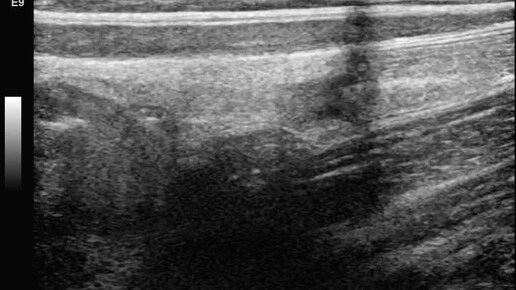

Ультразвуковые находки от врача УЗД Зорина Я.П.